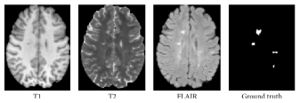

Publication: PLoS One. 2016 Nov 2;11(11):e0165302. PMID: 27806121 | PDF Authors: Porz N, Habegger S, Meier R, Verma R, Jilch A, Fichtner J, Knecht U, Radina C, Schucht P, Beck J, Raabe A, Slotboom J, Reyes M, Wiest R. Institution: Support Center for Advanced Neuroimaging, Institute for Diagnostic and Interventional Neuroradiology, University Hospital and University of Bern, Bern, Switzerland. Background/Purpose: Comparison of a fully-automated segmentation method that uses compartmental volume information to a semi-automatic user-guided and FDA-approved segmentation technique. METHODS: Nineteen patients with a recently diagnosed and histologically confirmed glioblastoma (GBM) were included and MR images were acquired with a 1.5 T MR scanner. Manual segmentation for volumetric analyses was performed using the open source software 3D Slicer version 4.2.2.3. Semi-automatic segmentation was done by four independent neurosurgeons and neuroradiologists using the computer-assisted segmentation tool SmartBrush® (referred to as SB), a semi-automatic user-guided and FDA-approved tumor-outlining program that uses contour expansion. Fully automatic segmentations were performed with the Brain Tumor Image Analysis (BraTumIA, referred to as BT) software. We compared manual (ground truth, referred to as GT), computer-assisted (SB) and fully-automated (BT) segmentations with regard to: (1) products of two maximum diameters for 2D measurements, (2) the Dice coefficient, (3) the positive predictive value, (4) the sensitivity and (5) the volume error. RESULTS: Segmentations by the four expert raters resulted in a mean Dice coefficient between 0.72 and 0.77 using SB. BT achieved a mean Dice coefficient of 0.68. Significant differences were found for intermodal (BT vs. SB) and for intramodal (four SB expert raters) performances. The BT and SB segmentations of the contrast-enhancing volumes achieved a high correlation with the GT. Pearson correlation was 0.8 for BT; however, there were a few discrepancies between raters (BT and SB 1 only). Additional non-enhancing tumor tissue extending the SB volumes was found with BT in 16/19 cases. The clinically motivated sum of products of diameters measure (SPD) revealed neither significant intermodal nor intramodal variations. The analysis time for the four expert raters was faster (1 minute and 47 seconds to 3 minutes and 39 seconds) than with BT (5 minutes). CONCLUSION: BT and SB provide comparable segmentation results in a clinical setting. SB provided similar SPD measures to BT and GT, but differed in the volume analysis in one of the four clinical raters. A major strength of BT may its independence from human interactions, it can thus be employed to handle large datasets and to associate tumor volumes with clinical and/or molecular datasets ("-omics") as well as for clinical analyses of brain tumor compartment volumes as baseline outcome parameters. Due to its multi-compartment segmentation it may provide information about GBM subcompartment compositions that may be subjected to clinical studies to investigate the delineation of the target volumes for adjuvant therapies in the future. |

Set of MRI sequences used in this study for manual, automatic, and semi-automatic tumor volumetry. Original T1-weighted post-contrast MRI slice (A), manual subcompartmental segmentation into non-enhancing tumor (green), enhancing tumor (blue), and necrotic tissue (red) (B). BT subcompartmental segmentation into non-enhancing tumor (green), enhancing tumor (blue) and necrotic tissue (red) (C). BT core tumor segmentation (dark blue, D), SB1 core tumor segmentation (light red, E), SB2 core tumor segmentation (green, F), SB3 core tumor segmentation (purple, G) and SB4 core tumor segmentation (yellow, H). |